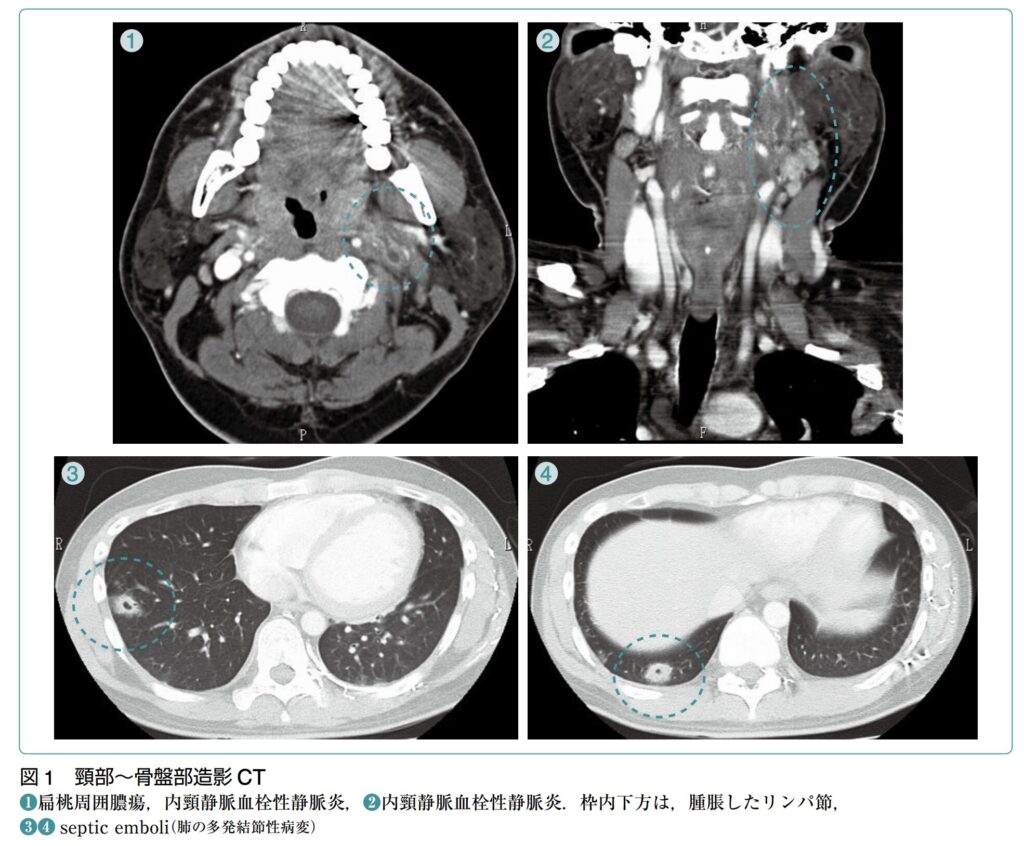

病態

- Lemierre症候群は、口腔や咽頭領域の感染に続発して引き起こされる、内頸静脈の化膿性血栓性静脈炎です。

- 多くの場合、口蓋扁桃や扁桃周囲組織での初期感染から始まります(歯からの感染や中耳炎、副鼻腔炎が原因となることは比較的まれです)。

- 感染が咽頭スペースや内頸静脈へと進展し、1〜3週間の期間を経て感染性血栓を形成します。この血栓形成には、扁桃の静脈流や傍咽頭間隙へのリンパ流を介した感染波及、あるいは先行するウイルス・細菌感染による咽頭粘膜の障害が、原因菌(F. necrophorumなど)の侵入を容易にしている可能性が指摘されています。

- なお、Lemierre症候群の病態の主体は内頸静脈の感染性血栓ですが、炎症の波及により外頸静脈などの周囲の静脈にも血栓が生じ得るようです。

- 遠隔臓器への転移:内頸静脈に形成された感染性血栓から細菌が血流に乗って散布され、肺を中心とした遠隔臓器への転移性感染(敗血症性塞栓)を引き起こすのが本疾患の重大な特徴です。

- 進行期(肺への波及):感染が進行すると高頻度で肺に遠隔感染巣を形成し、呼吸困難、胸膜炎症状、喀血などを引き起こします。具体的には、敗血症性肺塞栓による壊死性空洞病変、膿胸、肺膿瘍、縦隔洞炎といった重篤な肺合併症をもたらします。

- 造影の頸部~胸部CT検査が最も有用です。

- Lemierre症候群の診断は、血液培養検査の結果(嫌気性菌群の検出など)とあわせて、患側の内頸静脈内に血栓性病変が画像的に確認できることが一般的な決め手となります。

- 頸部~胸部造影CT検査:診断において最も中心となる検査です。内頸静脈内の陰影欠損や血栓を的確に評価することができます。さらに、胸部まで含めて撮影を行うことで、Lemierre症候群に高頻度で合併する遠隔感染巣である肺病変(多発性の空洞を伴った結節影など)の有無も同時に確認することができます。